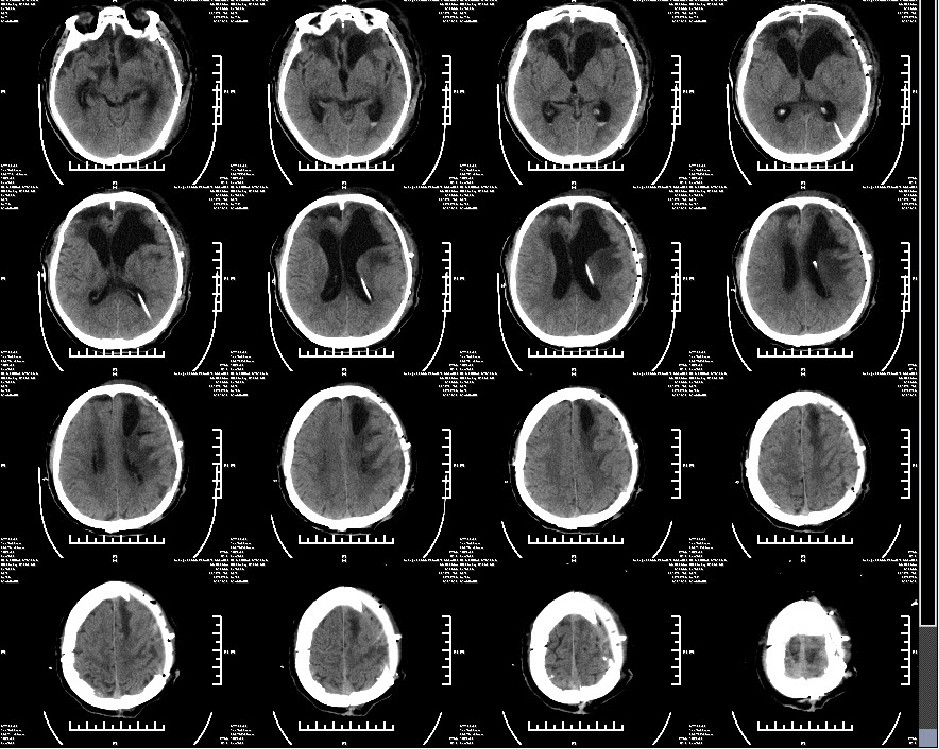

2019年2月12日患者出院头颅CT

查体:GCS评分:4-1-4=9分,双瞳孔等圆等大,直径约2.0mm,对光反射存在。病理征阴性。转康复医院继续治疗。

2019年4月18日头颅CT:行颅骨修补+VP-分流术

2019年4月30日术后头颅CT

患者半年后随访